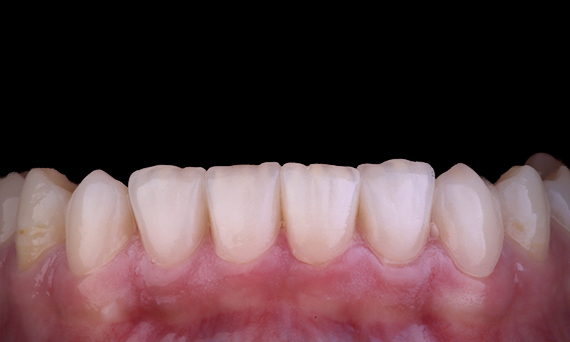

Aesthetic Rehabilitation of Amelogenisis Imperfecta

CEREC Tessera

An esthetic rehabilitation in the anterior region could be realized with labside CEREC Tessera restorations veneered with Celtra Ceram.

Before: The treatment objective was to rehabilitate the anterior maxilla and mandible for esthetic improvement. The clinical diagnosis revealed ameloenesis imperfecta.

After: Labside- fabricated restoration made from advanced lithium-disilicate ceramic CEREC Tessera and for the high esthetic result, the veneering with Celtra Ceram.

Sabine Mayer (CDT)

Koblenz, Germany

Mario Pace (CDT)

Lahnstein, Germany